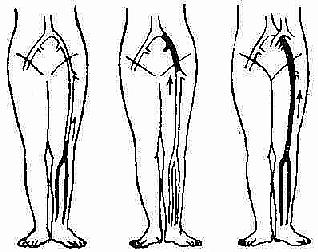

下肢深静脉血栓形成,可发生在下肢深静脉的任何部位。临床常见的有两类:小腿肌肉静脉丛血栓形成和髂股静脉血栓形成。前者位于末稍,称为周围型;后者位于中心,称为中央型。无论周围或中央型,均可通过顺行繁衍或逆行扩展,而累及整个肢体者,称为混合型,临床最为常见(图2-120)。

(1)周围型 (2)中央型 (3)混合型

图2-120 下肢深静脉血栓形成的类型